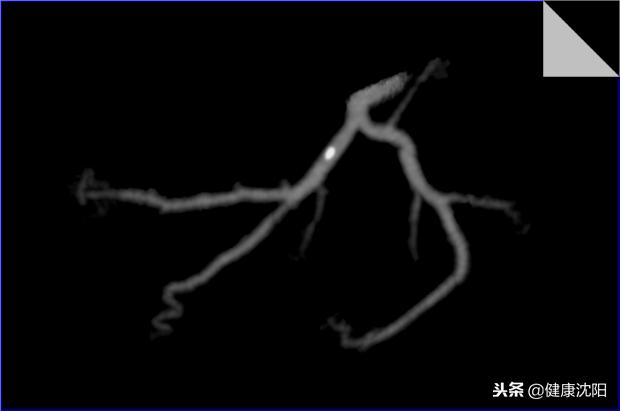

简单地说就是将不在同一片面的组织或血管重组到一个平面上显示的技术。它能显示血管壁、血管腔内的病变,可以判断有无斑块,斑块的性质,血管与周围组织的关系等等,当VR、MIP发现管腔狭窄或扩张时,可以通过CPR明显病因。探针技术是在CPR拉直血管的基础上,探测感兴趣区域的血管内壁情况的技术。

df:显示血管曲面、拉直图像,观察到血管内闭塞及狭窄情况